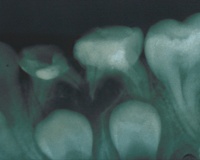

Для уточнения типа хронического пародонтита делается рентген зуба с окружающими тканями:

• В гранулирующей форме заметен очаг потери костной массы, нарушение целостности корковой пластинки с нечеткими границами.

• Гранулематозный вариант характеризуется четко выраженной круглой или овальной областью поражения.

• При фиброзном периодонтите врач обнаруживает расширение щели в апикальной области.